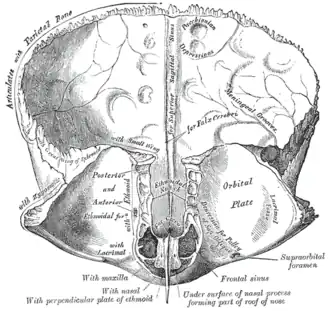

Frontal bone. Inner surface. (Trochlear fovea not directly labeled, but visible at bottom right.) | |

The trochlear fovea is a slight depression on the anteromedial orbital surface of the orbital plate of the frontal bone. Attached to the trochlear fovea is the trochlea of the superior oblique muscle.